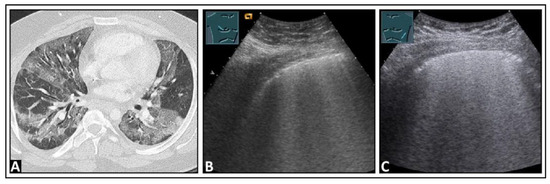

5. Pneumonia